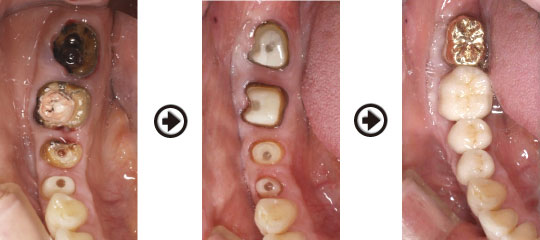

歯槽堤(歯肉)の陥凹を防ぐ為、抜歯部位に骨補填剤と軟組織を移植しました。

ファイバーコア(土台)を製作し、歯肉の成熟を待って、型取りを行います。